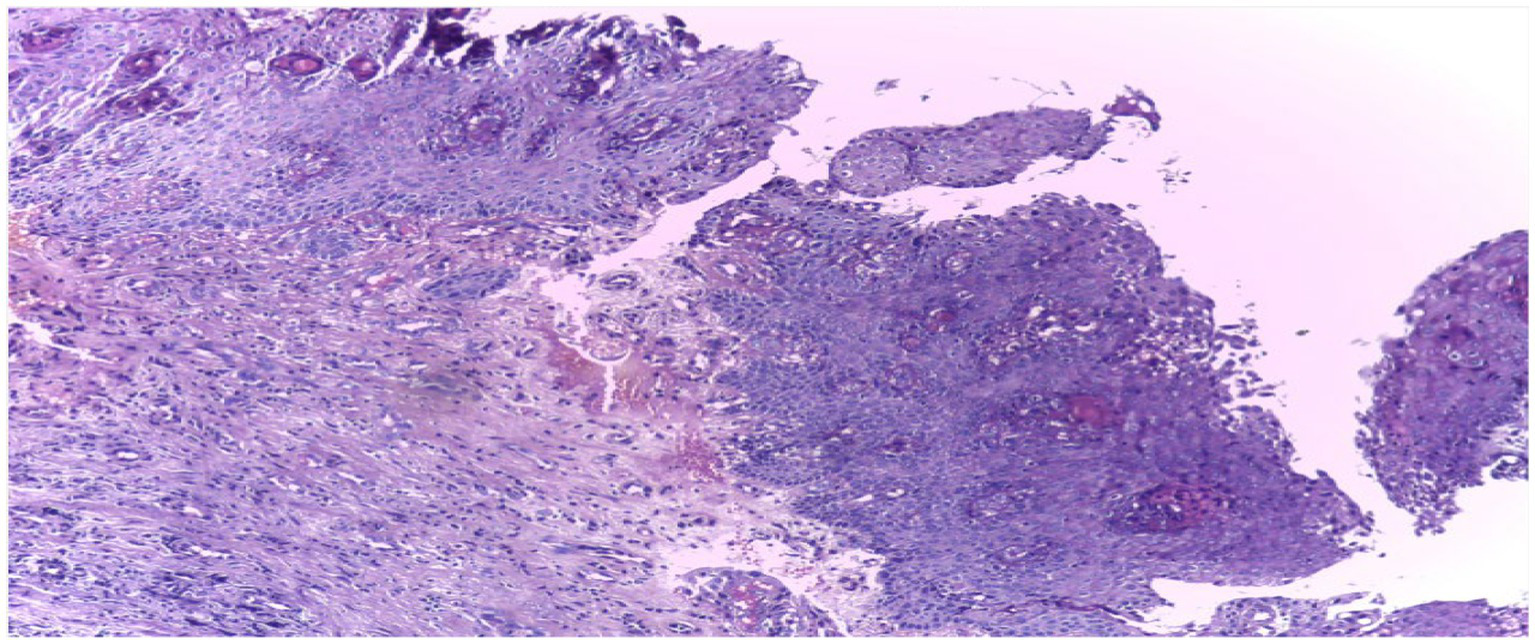

The organization of the dataset plays a vital role in the overall efficiency of the processing phase. To facilitate ease of access and processing, the images are meticulously sorted into separate directories based on their categorical classification – normal epithelium or OSCC. The structured arrangement is not solely for convenience; it stands as a strategic choice profoundly simplifying data management and labeling during the critical preprocessing phase. This approach sets the foundation for enhanced accuracy in subsequent analysis. Figure 3 shows some sample images.

Figure 3

Sample images from dataset under different magnification.

The dataset employed in this investigation comprises 1,224 publicly accessible images. These images are segregated into two distinct collections, each exhibiting varying resolutions. The initial collection encompasses 89 images displaying normal epithelial tissue of the oral cavity and 439 images depicting Oral Squamous Cell Carcinoma (OSCC) at a magnification level of 100x. Meanwhile, the secondary collection encompasses 201 images exhibiting normal oral epithelium and 495 histopathological representations of OSCC at a magnification of 400x. These images were captured via a Leica ICC50 HD microscope, utilizing H&E staining on tissue slides that were meticulously assembled, processed, and classified by proficient medical specialists, sourced from 230 individual patients (17). Image data distribution is shown in Table 2 and data description in Figure 2.